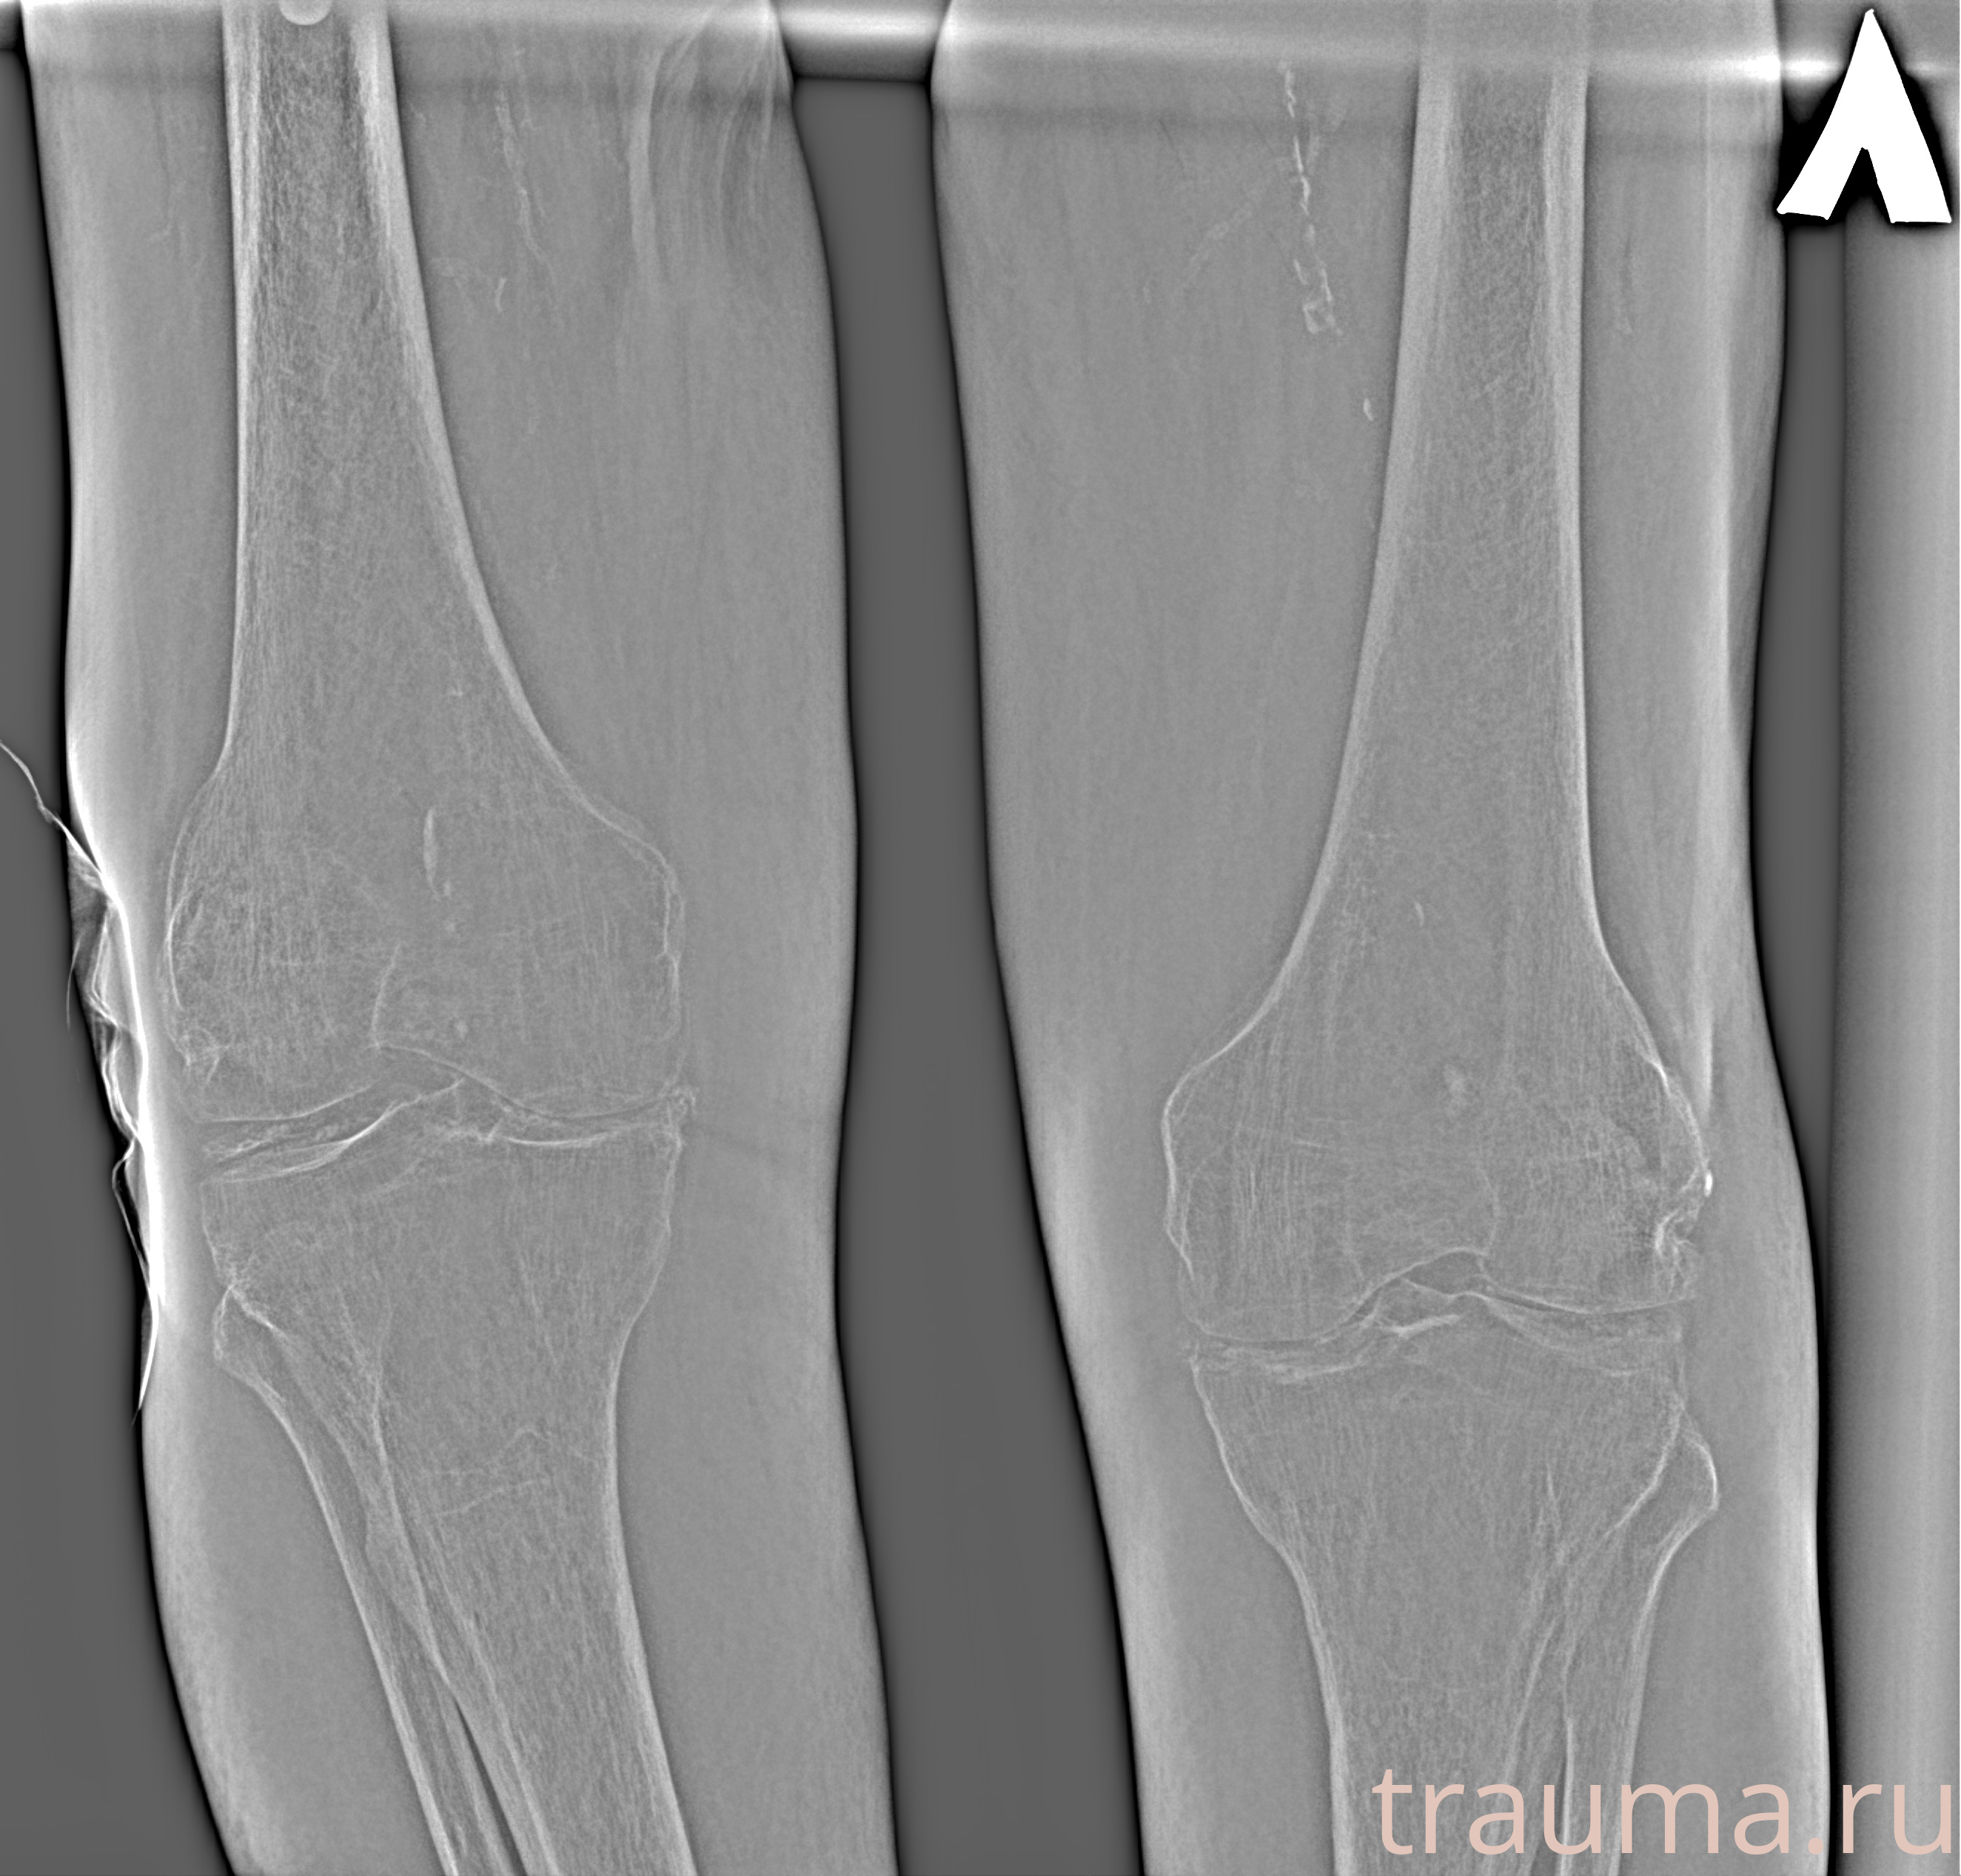

Рентгенограммы

Рентген на дому: по вашему адресу приезжает врач-рентгенолог, травматолог-ортопед с мобильным рентгеновским аппаратом, проводит диагностику травмы или заболевания, делает необходимые рентгенограммы, дает рекомендации по дальнейшему лечению. Получить качественные снимки в домашних условиях возможно благодаря уникальной методике, разработанной МосРентген Центром для института  Склифосовского